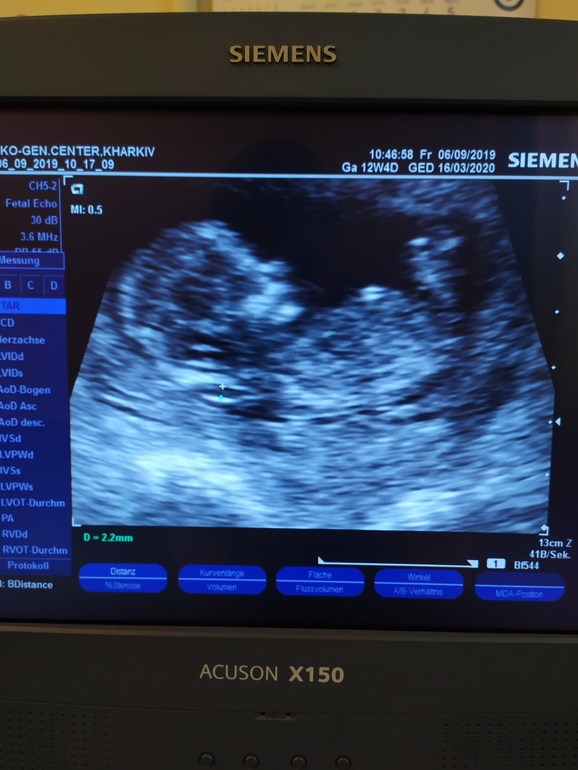

Всё о нашей беременностиВот и прошла я сегодня первый скрининг, переживала жутко, УЗИ длилось примерно минут 40-45, все дотошно измеряли, срок по УЗИ 12+4, Ктр 61 мм, твп 2,2, долго не могли определить правую маточную артерию, но все таки нашли, сдала сразу натощак кровь на биохимический скрининг, теперь на прием к врачу, сказали что с малышом по УЗИ все хорошо:)))))))

Нет, мне скан или нормы до 2,9 мм так что по УЗИ все норм и по биохимическому скринингу тоже все хорошо, низкие риски